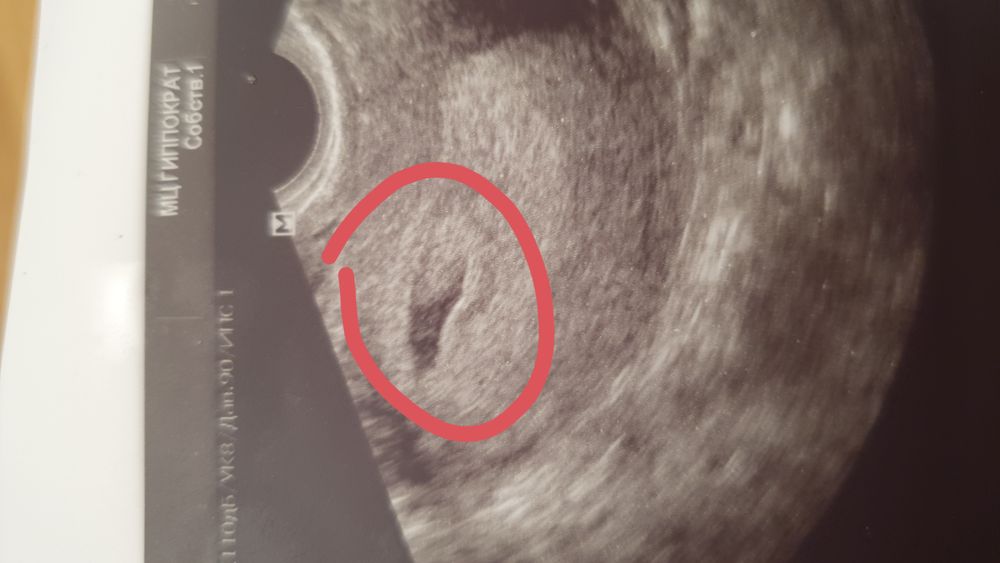

Изображение Эмбриончик, говорит, смотрите 😆 От овуляции 2 недели. Платная клиника. Для поднятия настроения вам) А ХГЧ пересдайте! Хочу дочку,